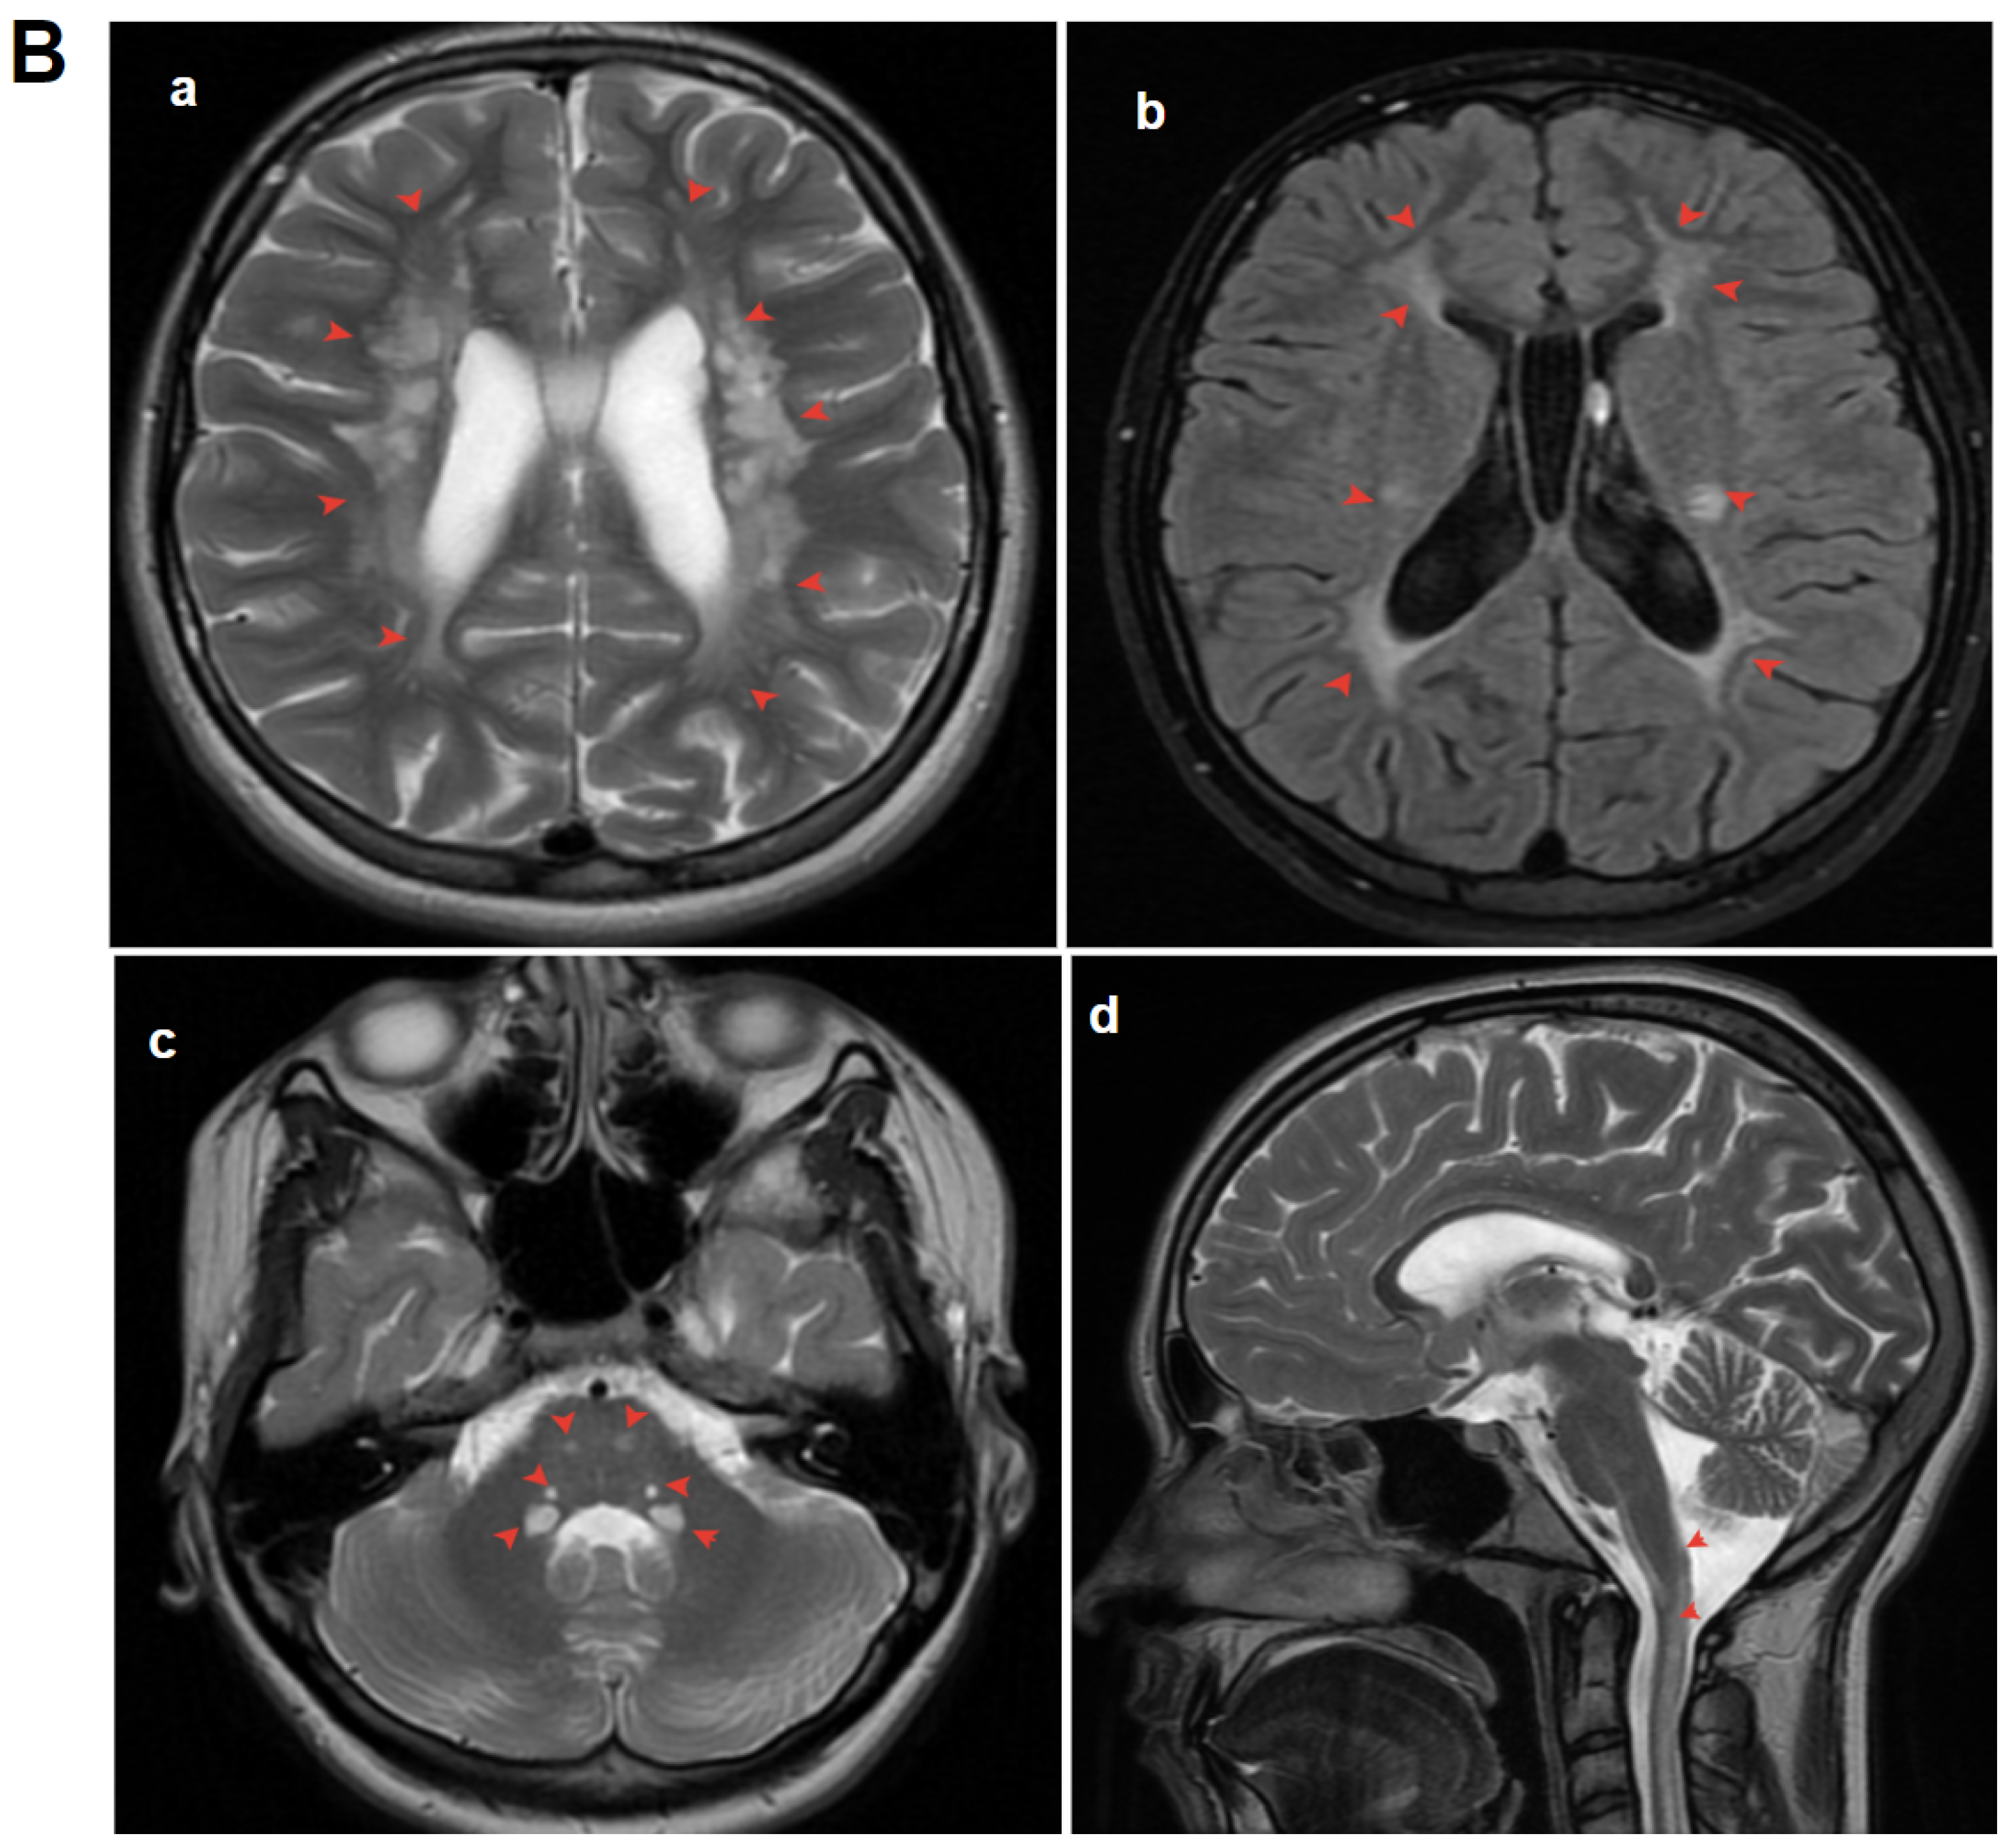

3.1.3. Patient 3